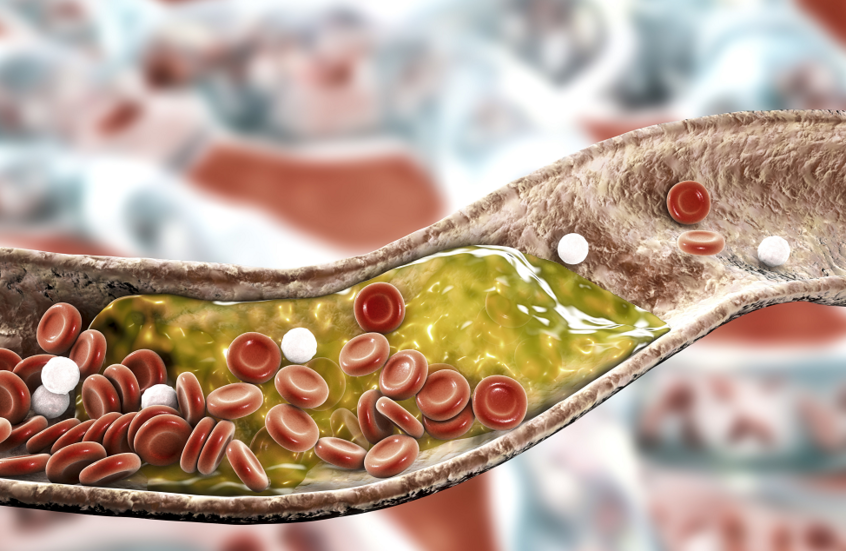

تحدث السكتات الدماغية عندما ينقطع إمداد الدم عن جزء من الدماغ، ولأنها تهدد الحياة، يجب التعامل معها كحالة طبية طارئة.

وتحدث السكتة الدماغية النزفية عندما ينفجر أحد الأوعية الدموية في الدماغ، وعادة ما ينتج عن ارتفاع ضغط الدم.

بينما تحدث السكتة الدماغية الإقفارية، وهي الأكثر شيوعا، عندما ينقطع تدفق الدم إلى الدماغ ما يؤدي إلى موت خلايا الدماغ.

وتحدث هذه الأنواع من السكتات الدماغية بسبب انسداد أو خلل، حيث يشكل ارتفاع الكوليسترول وضغط الدم عاملين من عوامل الخطر للسكتة الدماغية.